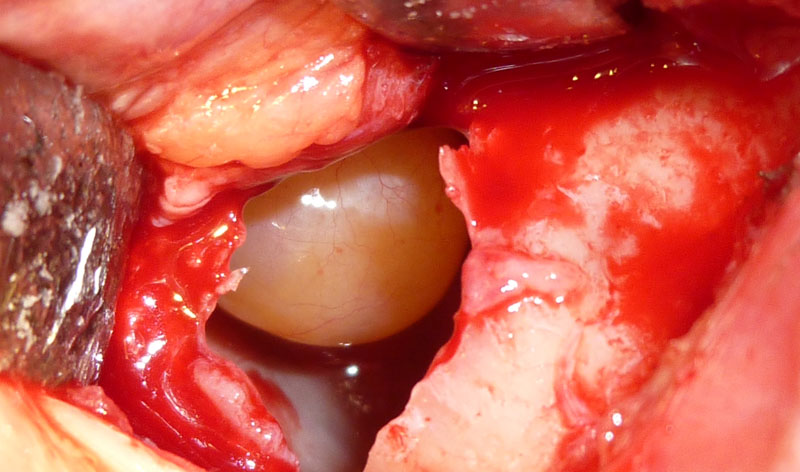

Es una bonita cirugía cuyo fin primordial es la extirpación del tumor con los limites de seguridad necesarios que requieren la anatomía patológica de la lesión. Sin embargo además de realizar una amplia extirpación , es esencial después reconstruir en la misma intervención, de forma adecuada y estética la cara operada para que el paciente pueda seguir teniendo una vida normal sin complejos y se disimulen las cicatrices para que no se noten nada.

Cuando estos tumores solo afecta a piel se pueden operar bajo anestesia local y sedación, sin embargo cuando afectan a partes óseas la anestesia general es necesaria.